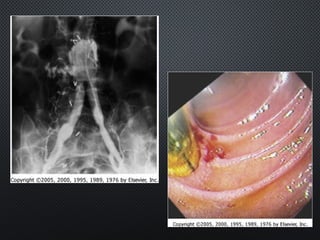

Angio = luminogram

thrombus lumen